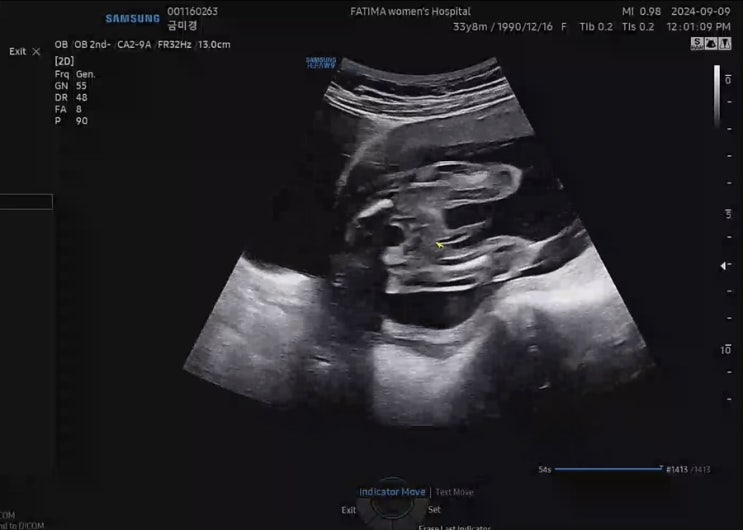

[임신 기록 : 둘째] 19주 23주 임신 기록. 파티마 여성 병원 임당 검사. 정밀 초음파.

오랜만에 쓰는 19주 차, 23주 차 둘째 임신 기록! 장꼬맹을 출산했던 병원은 이제 분만을 안 한다고,, 분만...